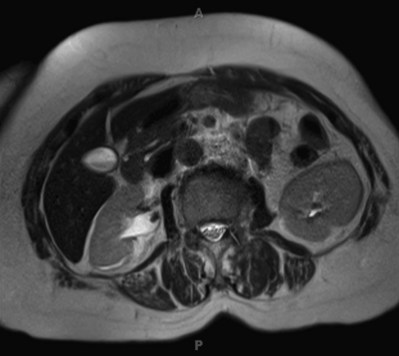

Therefore, at present, the most accurate method to estimate the volume of a staghorn calculus is CT with three-dimensional reconstruction. This technique permits highly accurate determination of stone volume as well as the three linear dimensions of renal calculi and correlates well with the actual volume of the stone, as measured by water displacement (Lam et al, 1992c). Thiruchelvam and coworkers (2005) reported that an added benefit of three-dimensional image reconstruction is in planning for subsequent percutaneous stone removal. However, three-dimensional CT reconstructions are costly, time consuming, and not widely available, thus limiting the utility of this technology. Nadler and associates (2004) have reported the use of coronal reconstructions of axial CT images to calculate the craniocaudal length of stones, which can facilitate more economical stone volume calculations.

Although CT attenuation values can distinguish some stone types in vivo, such as uric acid from calcium stones, the use of attenuation values alone results in considerable overlap; the range of values for calcium oxalate monohydrate and struvite stones does not allow these types to be confidently distinguished. Furthermore, it is not certain that the ease with which a stone is fragmented by SWL can be predicted by knowing only the major mineral composition of the stone. For example, cystine stones, which are considered difficult to break, have been shown in certain cases to break easily (Bhatta et al, 1989). Williams and associates (2003), too, reported that the variability in stone fragility to shockwaves is large, even within groups defined by mineral composition. It is likely that this variability in fragility could be due to variation in stone composition or structure, including variable amounts of secondary mineral in the stone, variation in the spatial arrangement of the secondary mineral within the stone, and variation in the layer structures of the primary and secondary minerals within a stone. Williams and associates (2002) also reported that displaying the data acquired by helical CT with use of bone windows can reveal remarkable internal structural detail of kidney calculi (Fig. 48–4 on the Expert Consult website

). It is clear that CT provides a wealth of information about stone characteristics. However, additional work is needed to determine the utility of this powerful imaging tool in determining the susceptibility of a given stone to SWL.

Figure 48–4 Photographic and helical CT images show structural variability in stones of the same type. Note that although all stones depicted are calcium oxalate in type, some have a mottled structure and others have a lamellar structure.